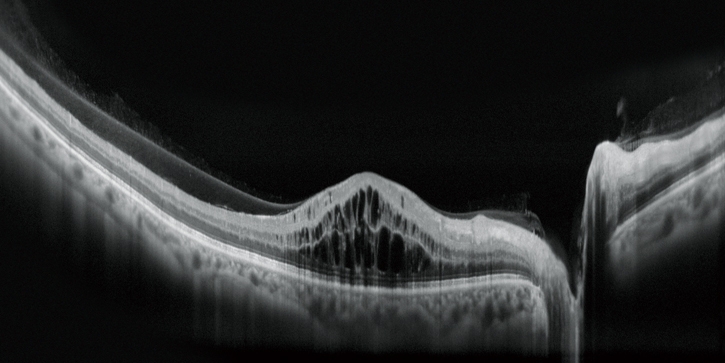

高清廣域OCT*

Mirante的掃描區域可達16.5 x 12毫米,單次拍攝就可實現包括黃斑和視盤的廣域診斷。超精細模式和高清自動追蹤功能可提供從玻璃體到脈絡膜的高質量圖像來觀察細微的病理改變。

AngioScan OCT-A血管造影(可選)